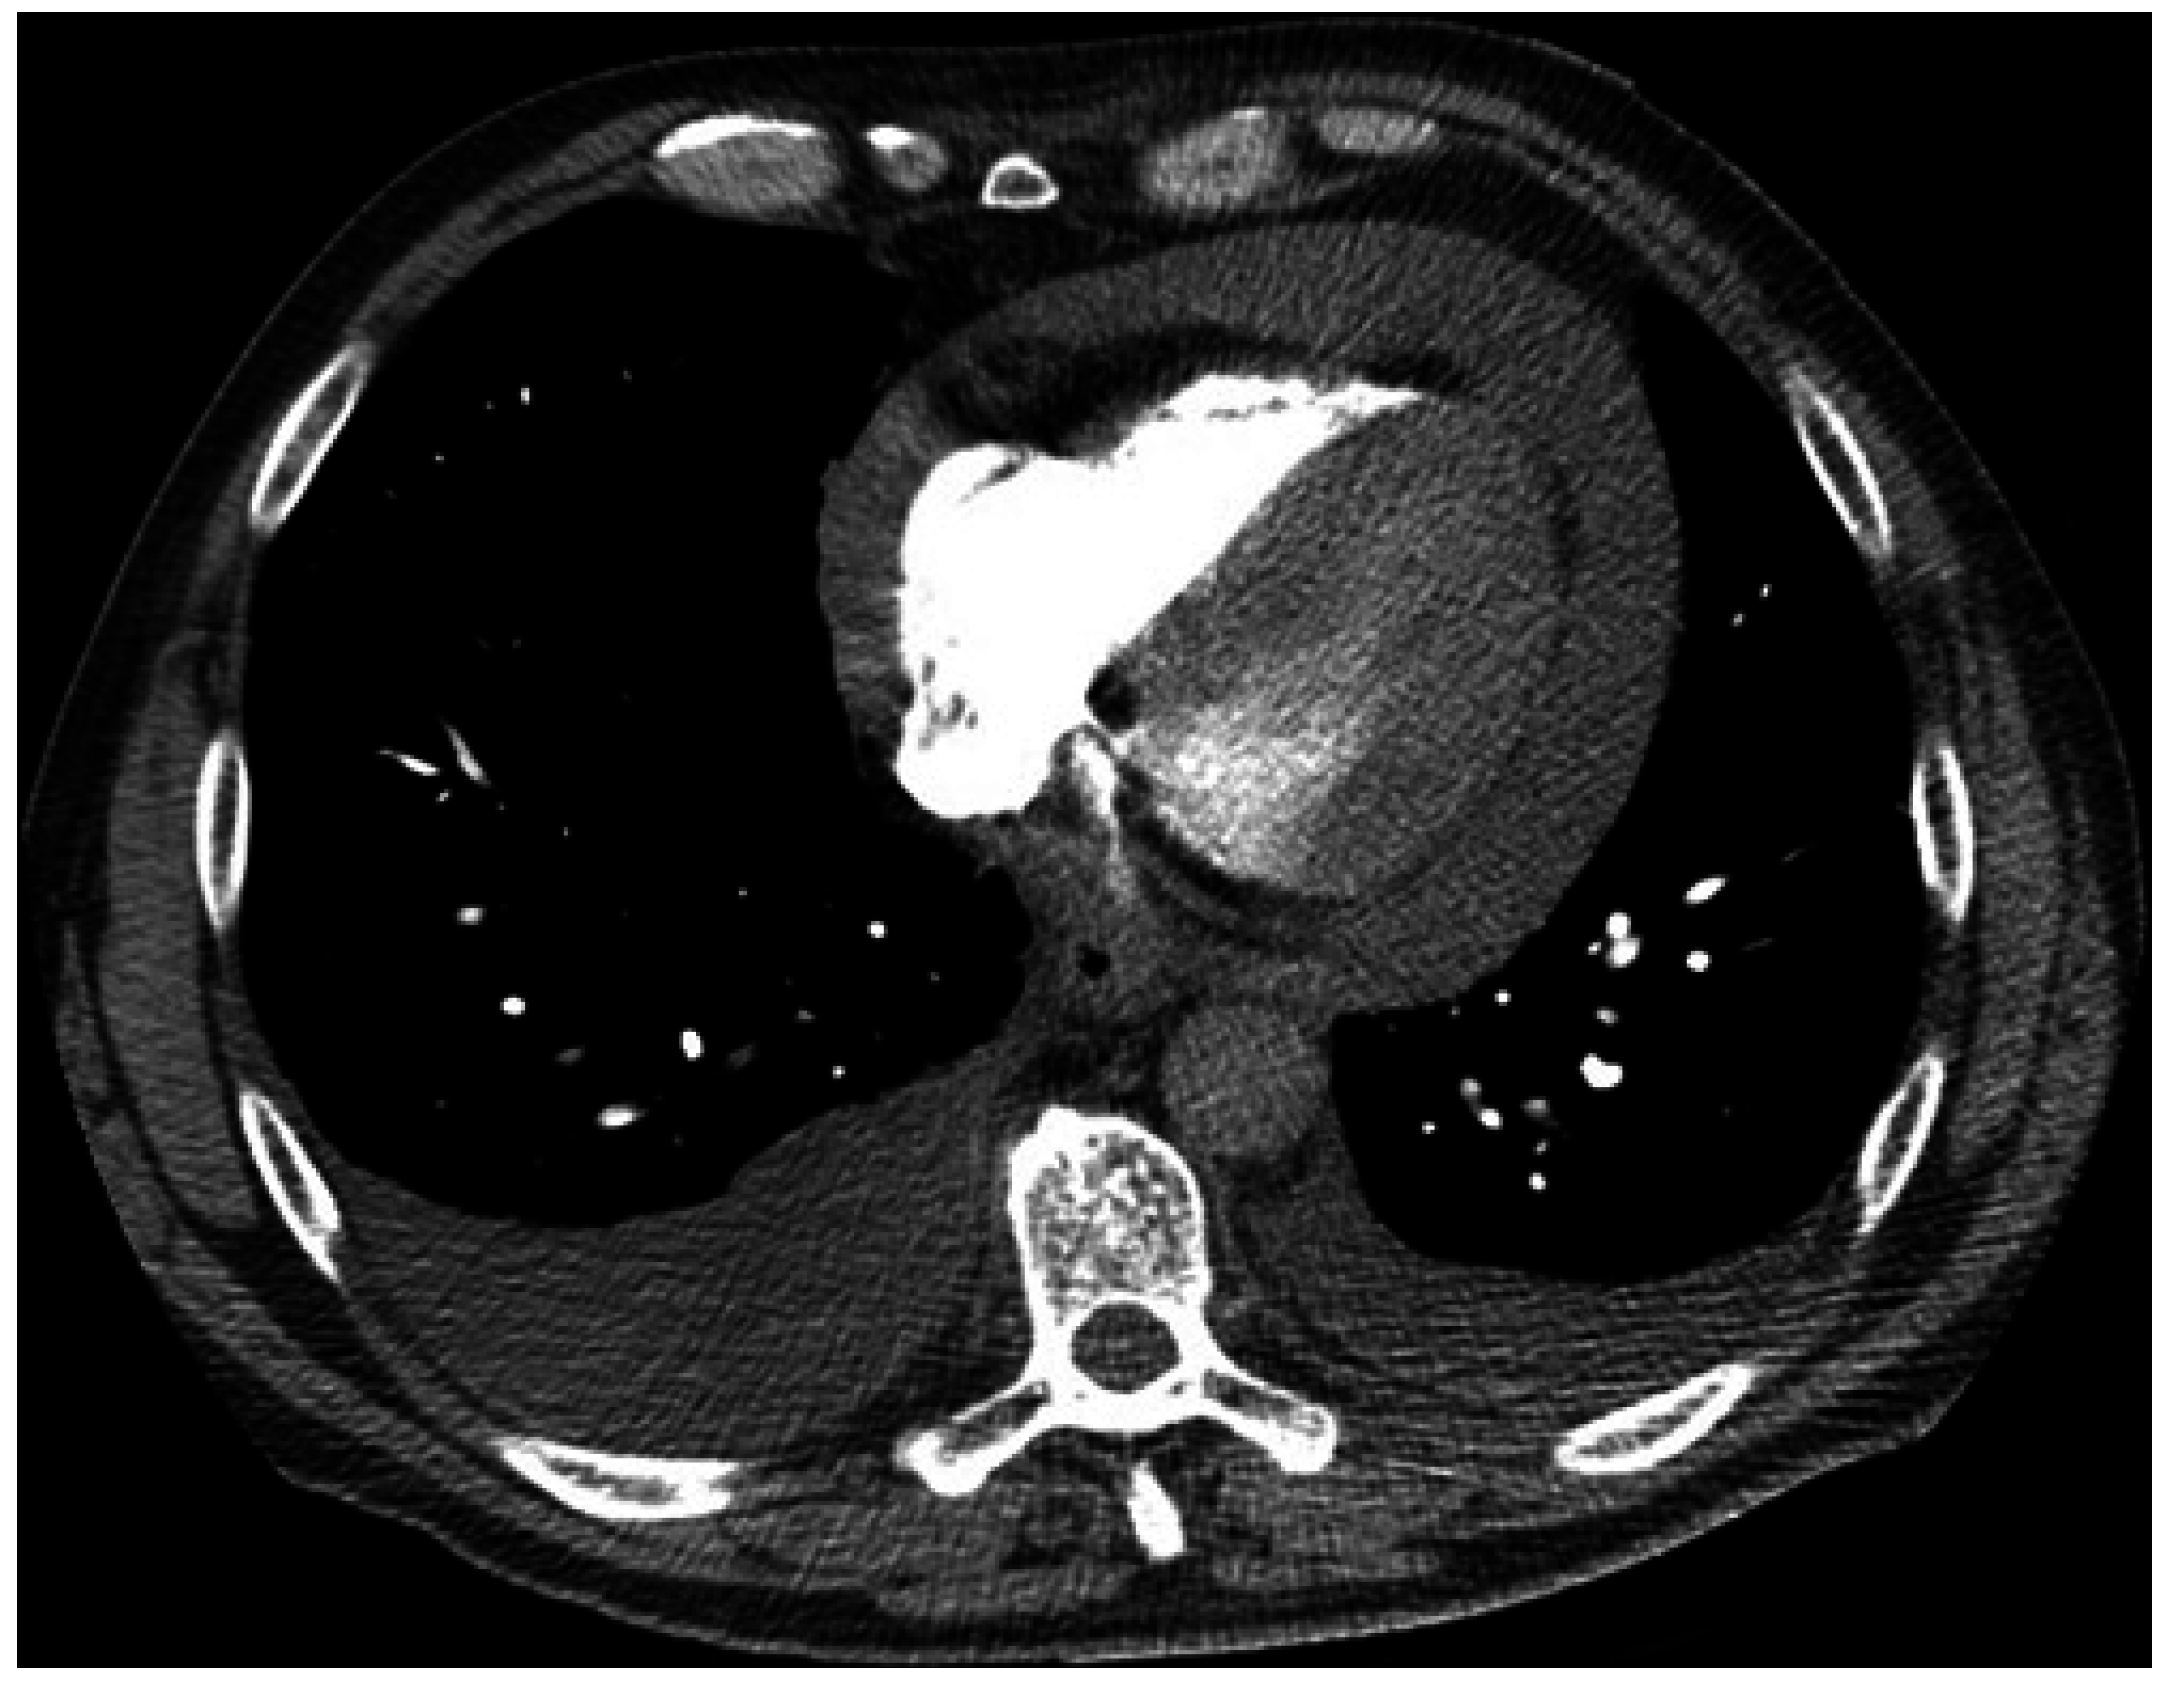

2. Case 1